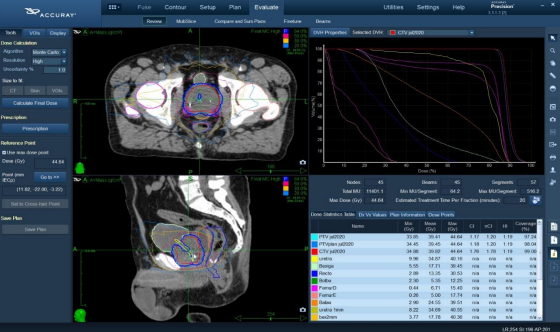

Figure 2: Example of a radiotherapy treatment planning

Figure 2

Planning and plan comparison: NVB volumes (OARs) were generated according with the POTEN-C clinical trial (Prostate Oncologic Therapy While Ensuring Neurovascular Conservation - NCT03525262) in both pre and post HAS CT scans, consisting of the neurovascular bundle, penile bulb and pudendal arteries. Planning Organ at Risk Volume (PRV) represents a 3mm expansion from NVB volume. Prostate GTV represented MR defined dominant radiographic disease, CTV as the full prostate with the insertion of the seminal vesicles, PTV defined as CTV+5mm margin excluding the urethra with a margin of 1 mm to spare this volume. Dosimetric plans were generated on both scans (pre-spacer and post-spacer) for dosimetric comparison of NVB. Dose prescribed to the prostate was 35-37.5Gy in 5 fractions. Treatments plans were performed with MLC collimator for 11 patients and Iris for one patient. All plans were normalized to a dose prescription curve to ensure at least a 95% dose coverage to the PTV. The average prescription curve was 87.2% for pre-spacer ranging from 83.1% to 89.9%. For post-spacer plans, the average prescription curve was 83.2% ranging from 69.5% to 88.9%. All plans were calculated with Monte Carlo algorithm with a 1% uncertainty.